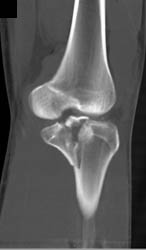

Diagnosis

CTA Shoulder With Arteriovenous (AV) Fistulae